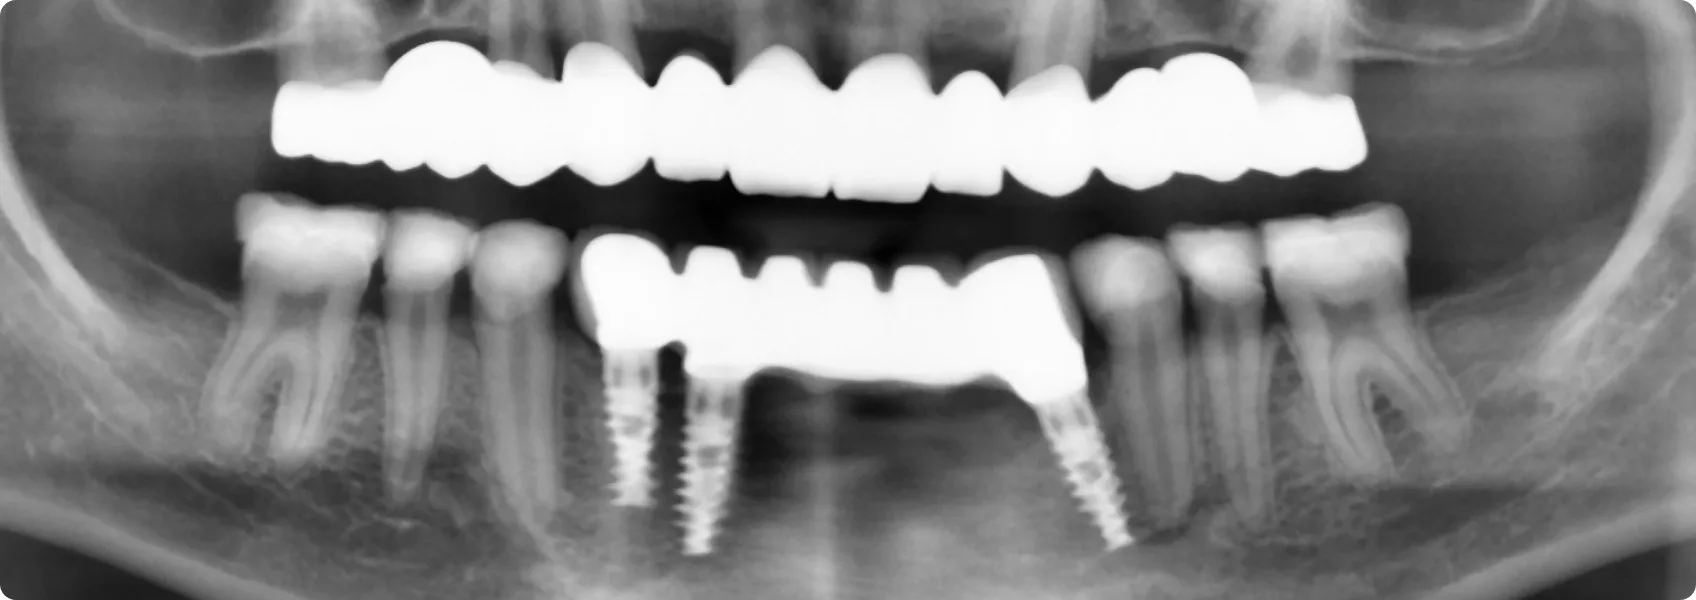

W odcinku przednim żuchwy (dolnej szczęki) braki zębowe były jednak zbyt rozległe, by oprzeć pracę tylko na własnych zębach. W tej sytuacji doktor Piotr zdecydował o wszczepieniu trzech implantów.

Te małe, tytanowe wszczepy, pełnią funkcję sztucznych korzeni. Zapewniają najwyższą możliwą stabilizację i bezpieczeństwo dla przyszłej pracy protetycznej w tej okolicy. Ostateczna rekonstrukcja to precyzyjnie zaprojektowane i wykonane przez techników dentystycznych uzupełnienie, które idealnie połączyło wsparcie na implantach ze wsparciem na naturalnych zębach.

Doktor Ewa krok po kroku, zaplanowała i zrealizowała finalną, kompleksową odbudowę protetyczną opartą zarówno na wszczepionych przez doktora Piotra implantach, jak i na starannie przygotowanych zębach własnych Pacjenta.